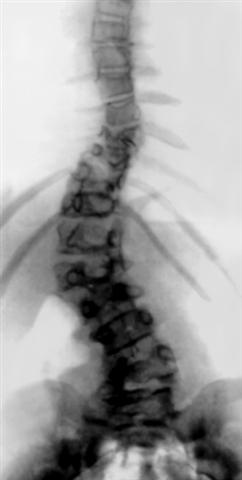

Рис. 2в). Врожденный сколиоз у больной 10 лет: рентгенограмма позвоночника (прямая проекция), локальное боковое искривление позвоночника связано с пороком развития позвонков (полупозвонки).